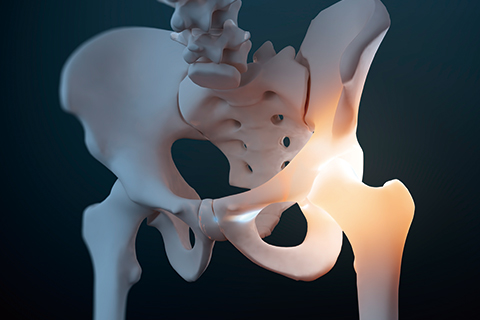

• 대퇴골두무혈성괴사

대퇴골로 가는 혈액 순환이 안 되는 병으로, 혈액 공급의 차단으로 인해 대퇴골두가 괴사되는 질환입니다.

대퇴골두무혈성괴사 치료방법

• 비수술적 치료 약물치료, 주사치료

• 수술적 치료 인공관절 치환술

• 고관절골절

충격을 받아 엉덩이 관절 주위가 골절되는 질환으로 골다공증 빈도가 높은 노인과 여성에게 주로 발생합니다.

고관절골절 치료방법

• 비수술적 치료 일반적으로 고관절 골절의 경우 비수술적 치료의 대상이 되는 경우는 매우 드뭅니다. 만성질환이나 암으로 인하여 여명 기간이 짧은 환자들에게 비수술치료가 행해지나 합병증, 관절 구축 등으로 높은 사망률이 있어 매우 신중하게 시행하는 치료입니다.

• 수술적 치료 고관절 골절 유합술, 인공관절 치환술